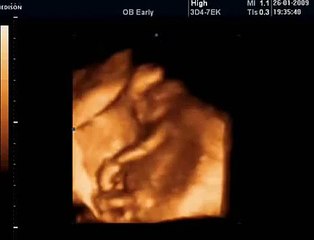

18 Haftalık Gebelik Bebek Ultrason Görüntüsü

Hafta hafta gebelik dönemi 18 haftalık bebek ultrason görüntüsü. Gebelikte 18. hafta daha çok bilgi için sayfamızı ziyaret edebilirsiniz.